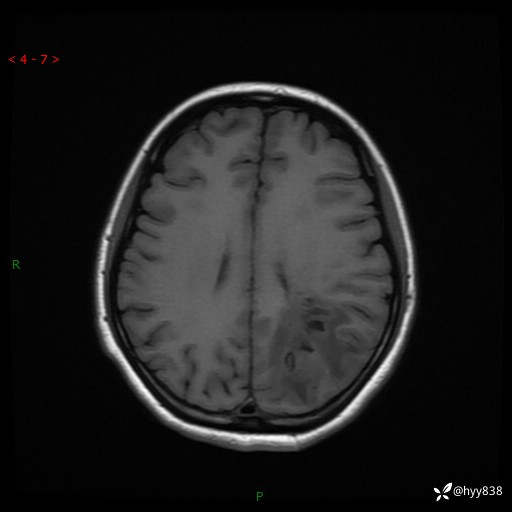

颅脑MRI平扫+增强